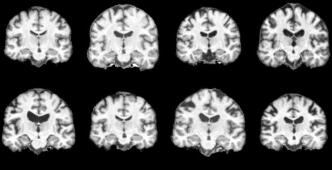

3D Brain MRIs We curate a dataset of about 27k datapoints for training with no diagnosed disease from the following datasets: ADNI petersen2010alzheimer , ABCD Study Karcher2021 ; Volkow2019 , HCP VANESSEN201362 , PPMI Pulliam2011 , and AIBL ELLIS2009672 . This task contains uncertainty in anatomical details such as ventricle sizes. Our setting employs demographic input conditions on age and binary sex (0: male, 1: female) and fine-tunes the Medical Open Network for Artificial Intelligence (MONAI) monai ’s optimized 3D LDM along with Rainbow training. We benchmark Rainbow against LDM and a GAN-based kwon2019braingan baselines. Rainbow’s graph generator module includes , , and .

Brain MRIs Figure 5 showcases the generated brain MRI images conditioned on a 65-year-old male individual. Unlike younger age groups (e.g. 10-20 years old) with characteristic small ventricles, or the older age groups (e.g. 70+ years old) with large ventricles alasar2019morphometric ; 10.1001/jamanetworkopen.2023.18153 ; 10.1001/archneur.60.7.989 , the 60s age range includes a wide variety of ventricle patterns raz2004aging , as visualized in Figure 5a with actual samples. While all models generated high-quality images, Rainbow effectively captures the diverse ventricle patterns with varying ventricle sizes, whereas the baseline LDM tends to produce similar ventricle regions across different samples. We provide full axial, coronal, and sagittal views for this experiment in Figure 28 and visibility of structures and details in generated 3D MRIs in Figure 27 in Appendix E.

In addition, we quantify brain MRI generations obtained from multiple tasks: image synthesis (with 200 conditions balanced on age and sex) and counterfactuals on age (three age shifts at 10, 40, and 80 years) and sex (flipping binary sex). For each task, we report FID score Seitzer2020FID and performance on age and sex prediction by pretrained classifier models (details at Appendix D.2). As shown in Table 1, Rainbow outperforms LDM and GAN baselines across all metrics and tasks with lower FID, higher sex accuracy, and lower age MAE. To justify age and sex prediction models, we report "Real" results that were tested on real data and "Random" results that were evaluated on random outputs. Figure 29 in Appendix E provides counterfactual generations.